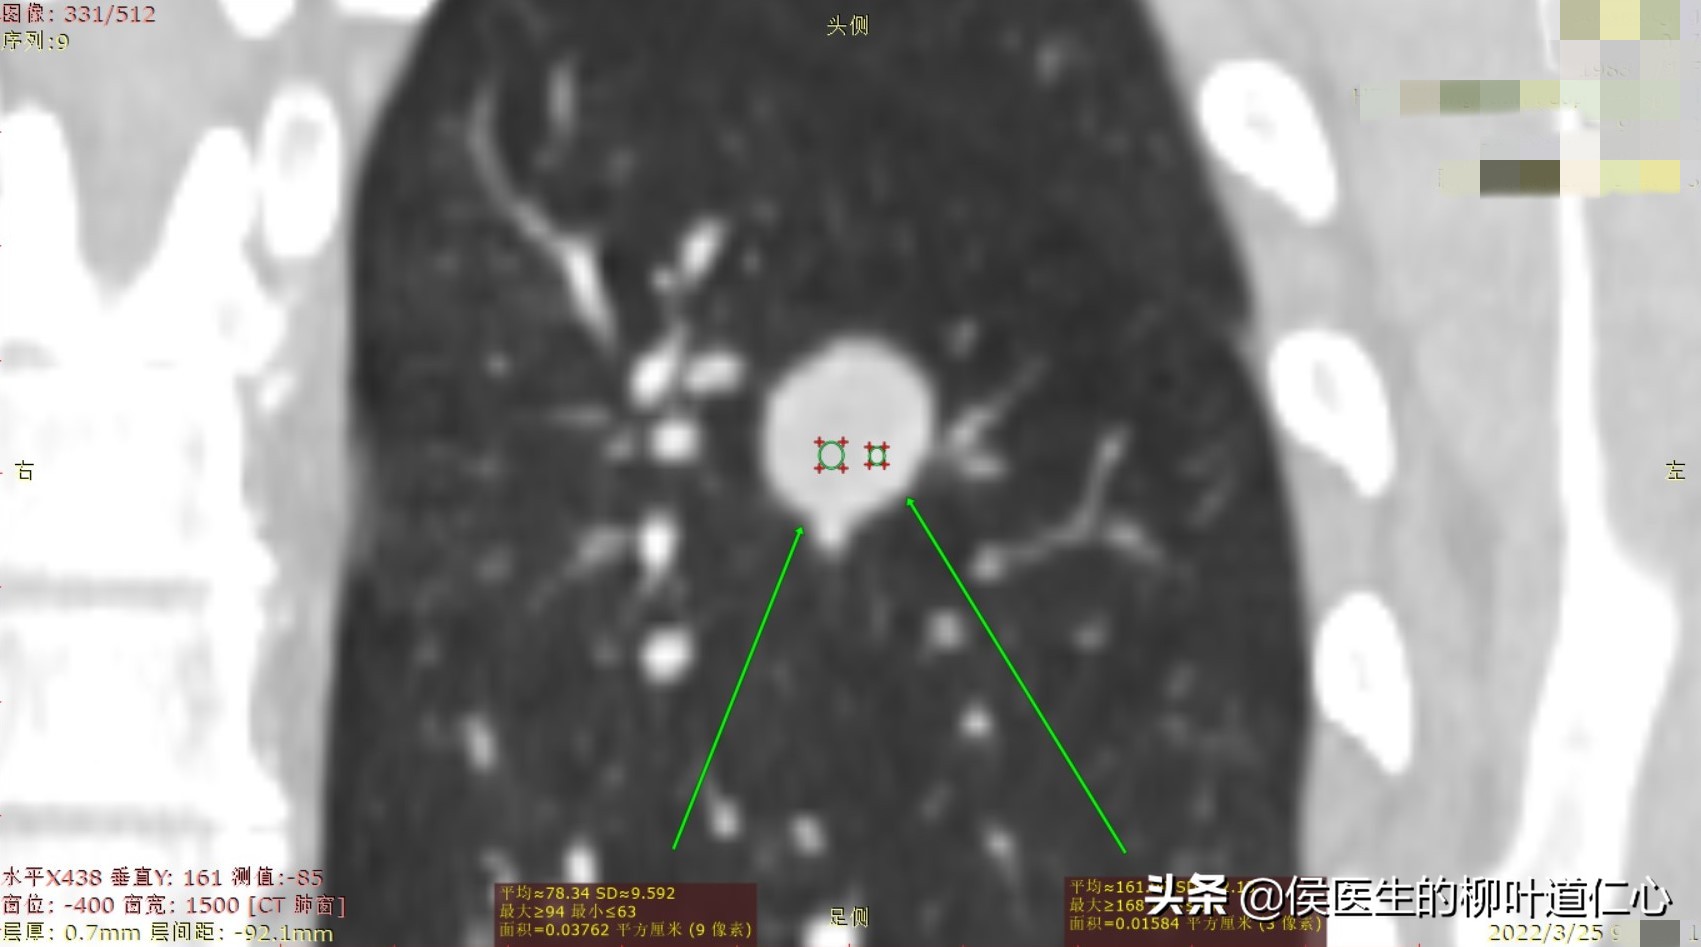

冠状位:

但细心地侯医生发现,所谓的增强后肺结节的强化,在“C+A"动脉期出现,而在”C+V“静脉期更为强化,这不是常规的肺恶性肿瘤的影像。

进一步进行VR的微血管重建,更能清晰的看到几乎一目了然的“血管旁开”,也就是血管均走行于肺结节的外部,相比于恶性肿瘤分泌“血管生成因子”促使新生血管的进入、紊乱、异常交通有很大的区别。

综合更多细节的甄别和量化分析,这一枚结节,我最终回复给同行朋友个人的影像诊断意见:良性肺血管性肿瘤,硬化性肺细胞瘤(硬化性血管瘤)首先考虑,恶性几率极小。